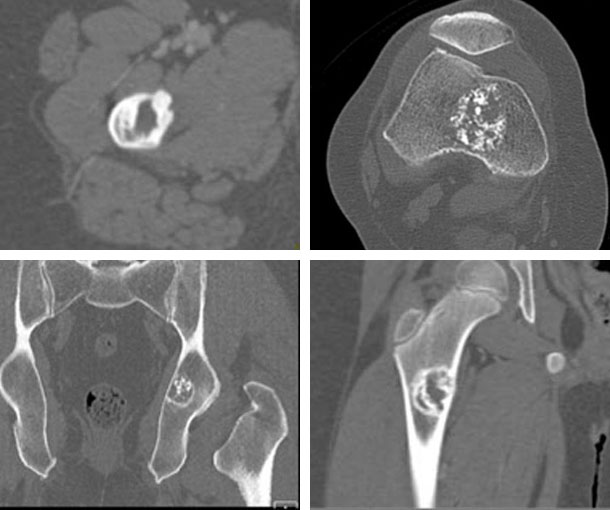

Enchondroma CT Findings

- Most common in the hands and feet but can also occur in the long bones

- Typically within the medullary cavity

- Small lesions (< 5cm)

- Calcifications may create stippled, popcorn, or ring-and-arc signs

- Soft tissue is never involved